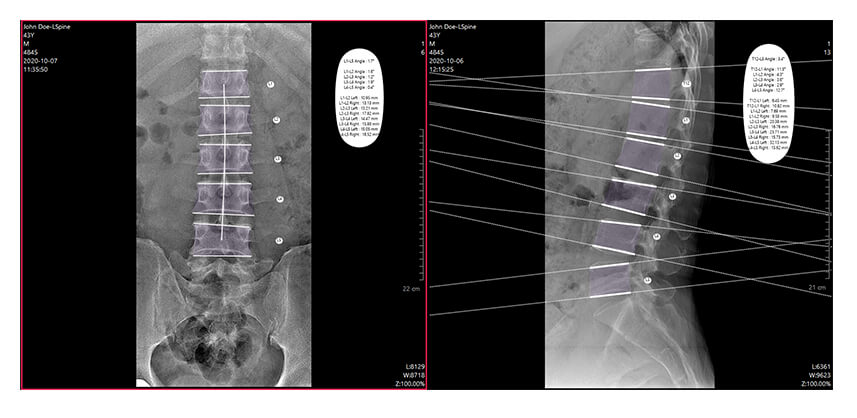

Comprehensive Chiropractic DR Analysis Tools

IQAspire DR panels come with IQView software to combine the superior image quality of Chiropractic DR with world-class Chiropractic Analysis Software.

Easy-to-use acquisition and image measurement tools with full DICOM integration makes IQView a comprehensive image management system for Chiropractic offices.

- User-friendly interface

- Comprehensive Chiropractic Toolset

- DICOM Integration

- Preloaded on laptop or PC

Just Some of the Standard Tools Available